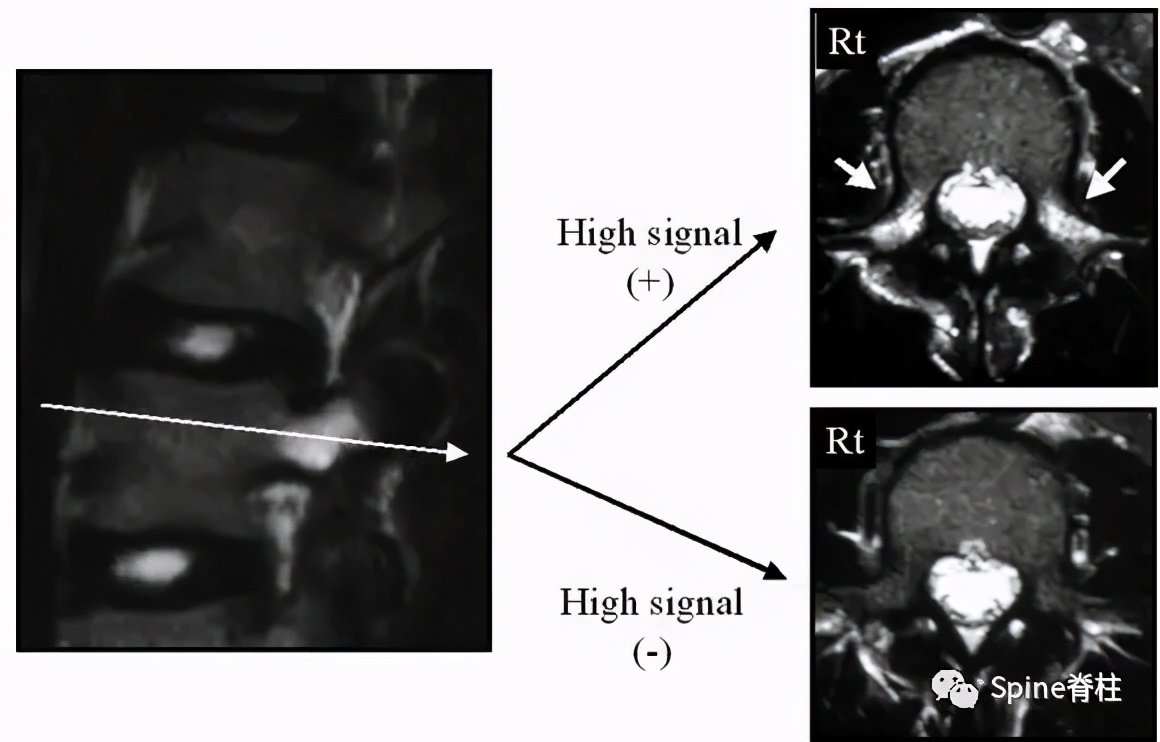

图:箭头所指为离断的椎体后缘

CT是诊断最有效的检查手段

- PARS的Takata分型:

图:A 型为分离部分含皮质骨,不伴椎体后方骨缺损(图A);B 型为分离部分较大,含皮质骨和松质骨,伴椎体后方较大骨缺损(图B);C 型为分离部分较小,含皮质骨和松质骨,伴椎体后方较小骨缺损(图C)。

由于对 腰椎椎体后缘离断症 (陈仲强)发生机理认识各异,有学者认为与青少年骺环未闭及运动创伤导致的椎体及骺环应力较大有关,也有学者认为是一种骨坏死,故命名尚未统一。

PARS 因与单纯 LDH 或 LSS 表现相似,临床易误诊或漏诊,并且 由于骨性致压因素的影响,PARS 患者的症状较单纯 LDH 严重 。对于经保守治疗无效,且存在神经根性症状或马尾神经损伤表现患者,应尽早手术治疗。